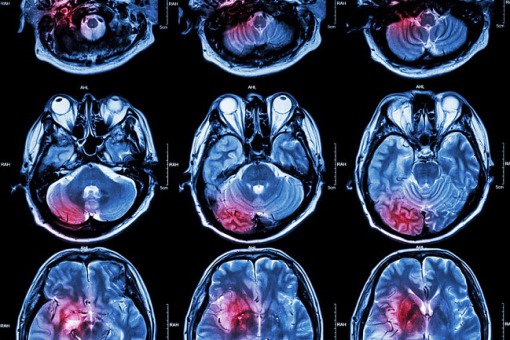

COVID-19 zwiększa ryzyko udaru mózgu

U blisko 22 proc. pacjentów z COVID-19 występują encefalopatia lub udar mózgu – wynika z badania przeprowadzonego przez Hiszpańskie Towarzystwo Neurologiczne (SEN). Wyniki badania zaprezentowano podczas międzynarodowego sympozjum naukowego.

Z analiz hiszpańskich badaczy z SEN, którzy swoje badanie przeprowadzili na 232 pacjentach zakażonych koronawirusem, wynika, że w przypadku 21,9 proc. z tych osób zanotowano wystąpienie encefalopatii (uszkodzenie mózgowia) lub udaru mózgu.